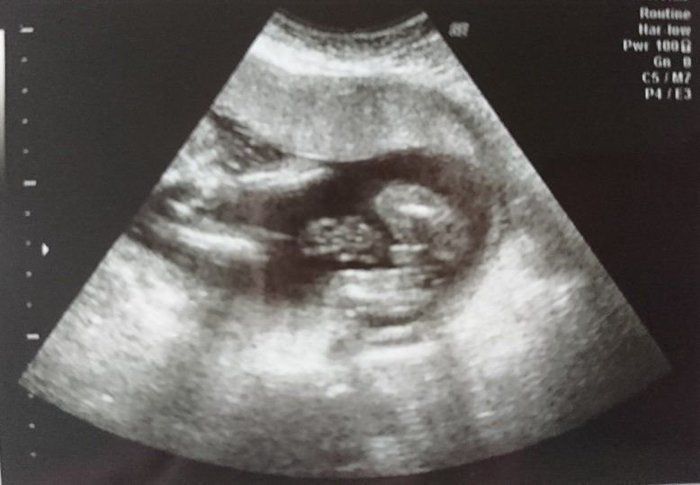

犬飼ねこさんの妊娠18週目のエコー写真

手の指がはっきりと見えます。